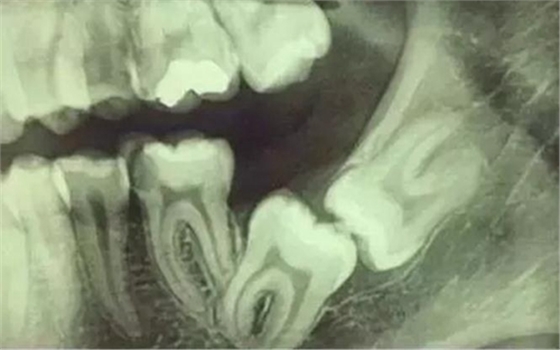

拍片是為了了解智齒周圍情況,也是為了了解智齒結(jié)構(gòu),牙根結(jié)構(gòu)千變?nèi)f化,有可能是融合成一個(gè)根,也可能是八爪根。不同牙根不同位置及方向,只有通過拍片來確認(rèn)。

通過拍片可以了解牙齒本身:生長方向,牙根數(shù)目,牙根是否彎曲,膨大等。

與重要解剖結(jié)構(gòu)的位置關(guān)系:如上頜磨牙與上頜竇的關(guān)系;下頜磨牙與下頜神經(jīng)管的關(guān)系;兒童在混合牙列期恒牙與乳牙胚的關(guān)系等??梢詼p少拔牙的風(fēng)險(xiǎn)。